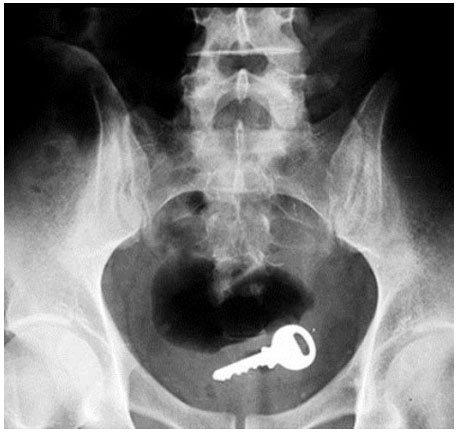

1-Uma chave

Perder as chaves é algo comum, mas chegar ao extremo de introduzi-las em seu próprio corpo para que isso não aconteça parece um pouco exagerado. De acordo com alguns relatos, esse é um dos objetos mais comuns encontrados dentro do corpo das pessoas, mas eles costumam entrar pela porta de cima.